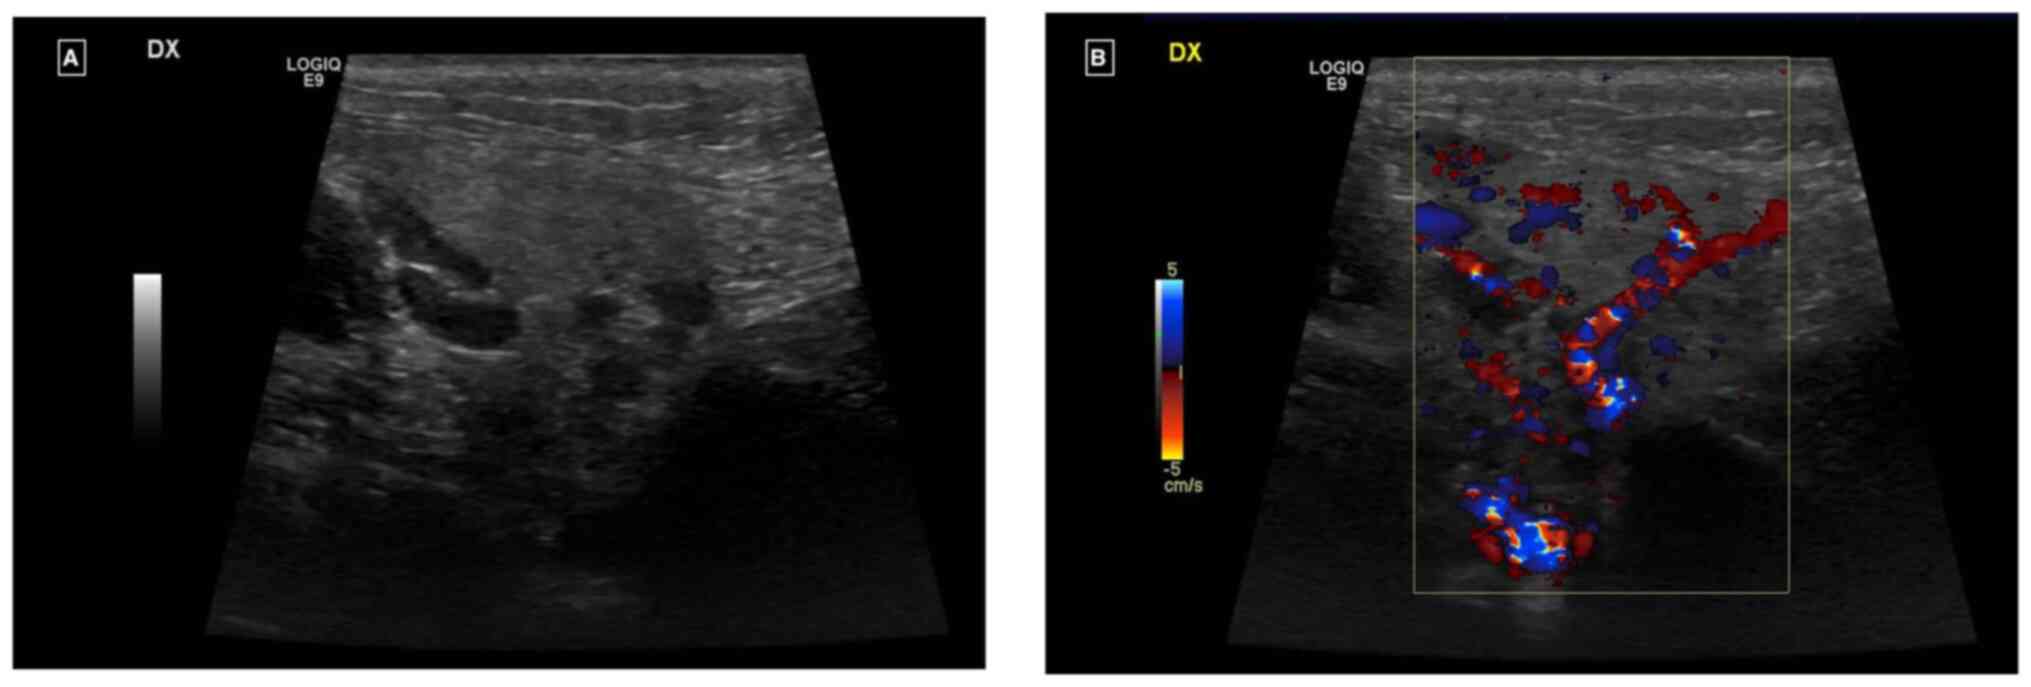

Ultrasound examination revealed an enlarged right parotid gland and right submandibular gland, both with a homogeneous echostructure and a diffused increase in echogenicity of the glandular parenchyma. There was also a diffuse increase in intraparenchymal vascularity and reactive adenitis. No fluid collection, obstructing stones, dilatation of salivary ducts, masses or abscesses were observed (Fig. 1A and B).

Figure 1

(A) Ultrasound and (B) Ecocolor-Doppler examination of the right parotid gland.